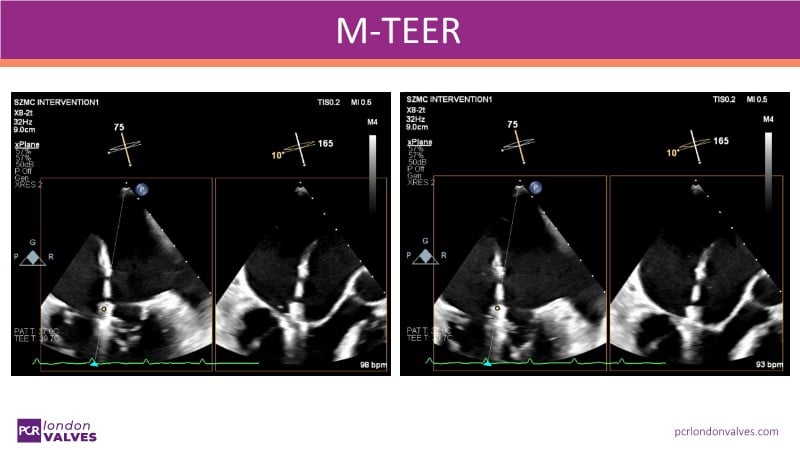

This LIVE case symposium brings mitral regurgitation guidelines into real clinical practice. Through step-by-step patient demonstrations and insightful discussion, the session explores how recommendations guide decision-making in ventricular and atrial secondary MR, how the heart team tailors therapy to individual anatomy and comorbidities, and how device iterations and procedural workflow can influence outcomes.